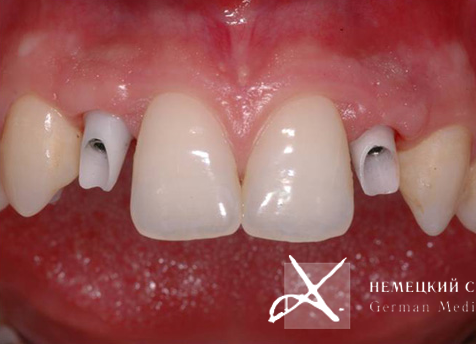

Учитывая достаточно высокую степень обнажения десны при улыбке, а также тонкий, "просвечивающий" тип слизистой оболочки, для обеспечения максимального эстетического результата выбрана индивидуально моделируемая эстетическая супраструктура (абатмент) на основе оксида циркония, выполненная по CAD/CAM-технологии.

Для устранения эффекта серой, синюшной десны выполнены эстетические безметаллловые оксидциркониевые реставрации. Представленные рентгенограммы демонстрируют успешную имплантацию и максимальную точность прилегания конструкции, а иллюстрации после окончания лечения убеждают в гарантированном достижении желаемого эстетического результата, в частности в наиболее сложной с точки зрения геометрии эстетики десневой зоне.